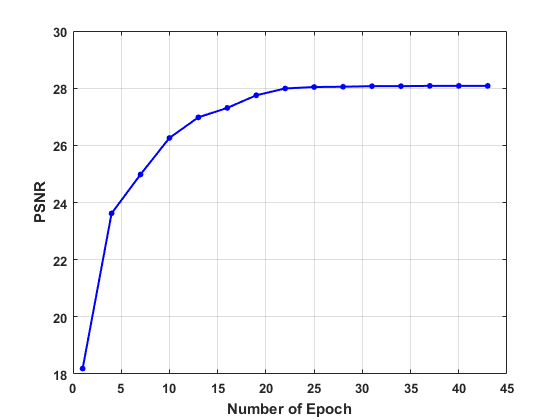

In the first place, we test the effect of the number of epoch on the convergence in network training on the human dataset. The values of the loss function, PSNR, and SSIM are plotted in Fig. 3, which evidence the convergence of our LRIP-net. Accordingly to plots, we fix the number of the epochs as during the training in the following experiments.